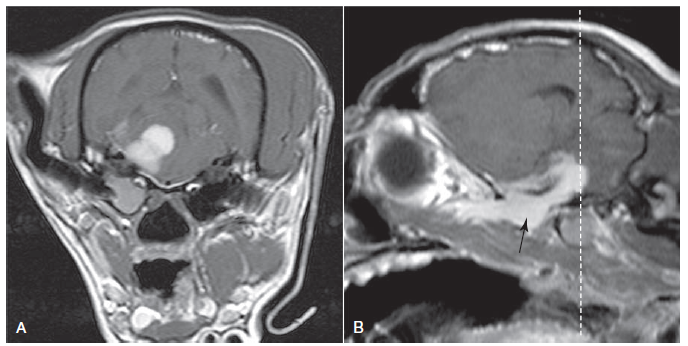

How would you describe this enhancement and what disease could it be?

A

Marked enhancement of the pachymeninges/dura but not of the sulci

Pachymeningitis (such as idiopathic hypertrophic)